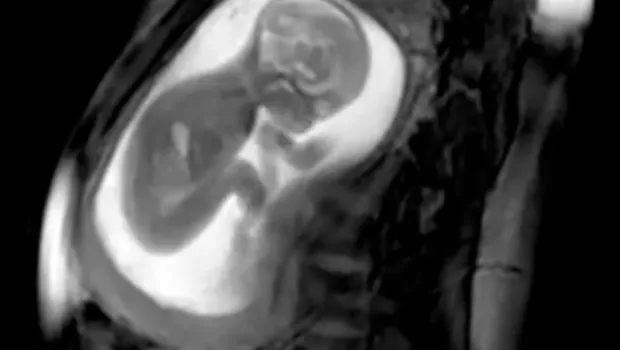

Czy dziecko w brzuchu ma czkawkę? Tak, to zjawisko jest całkowicie naturalne i nie powinno budzić niepokoju. Czkawka u płodu występuje, gdy dziecko łapczywie połyka płyn owodniowy, co prowadzi do podrażnienia przepony. W rezultacie pojawiają się niekontrolowane skurcze mięśnia oddechowego, które odczuwane są przez mamę jako delikatne wibracje lub podskoki w brzuchu.

Czkawka u dziecka w brzuchu to zjawisko, które może zaskoczyć przyszłe mamy. Jest to całkowicie naturalny proces, który nie powinien budzić niepokoju. Czkawka występuje, gdy płód łapczywie połyka płyn owodniowy, co prowadzi do podrażnienia niedojrzałej przepony. W efekcie pojawiają się skurcze, które matka odczuwa jako delikatne wibracje w brzuchu. Wiele kobiet zauważa te ruchy szczególnie w drugiej połowie ciąży, co może być dla nich zaskakującym, ale też kojącym doświadczeniem.

Czkawka u płodu to zjawisko, które jest całkowicie normalne i występuje często podczas ciąży. Jest to efekt połykania płynu owodniowego, co prowadzi do podrażnienia przepony. Kiedy dziecko w brzuchu połyka zbyt dużo płynu, jego przepona reaguje skurczami, co objawia się czkawką. Ten proces jest naturalny i świadczy o prawidłowym rozwoju układu trawiennego oraz oddechowego płodu.

Czkawka odgrywa kluczową rolę w rozwoju dziecka, szczególnie w kontekście układu oddechowego i trawiennego. W trakcie czkawki, dziecko stymuluje swoją przeponę, co pomaga w rozwijaniu mięśni oddechowych. To zjawisko wspiera rozwój płuc, umożliwiając lepsze przygotowanie do oddychania po narodzinach. Regularne skurcze przepony, które występują podczas czkawki, są formą treningu dla układu oddechowego płodu.

Czkawka odgrywa kluczową rolę w rozwoju układu oddechowego płodu. Podczas czkawki dochodzi do rytmicznych skurczów przepony, co stymuluje jej rozwój. Dzięki tym skurczom, mięśnie oddechowe są aktywowane, co jest ważne dla przyszłej zdolności dziecka do oddychania po narodzinach. Czkawka wspiera również rozwój płuc, umożliwiając ich lepsze przygotowanie do funkcji, które będą pełnić po urodzeniu.